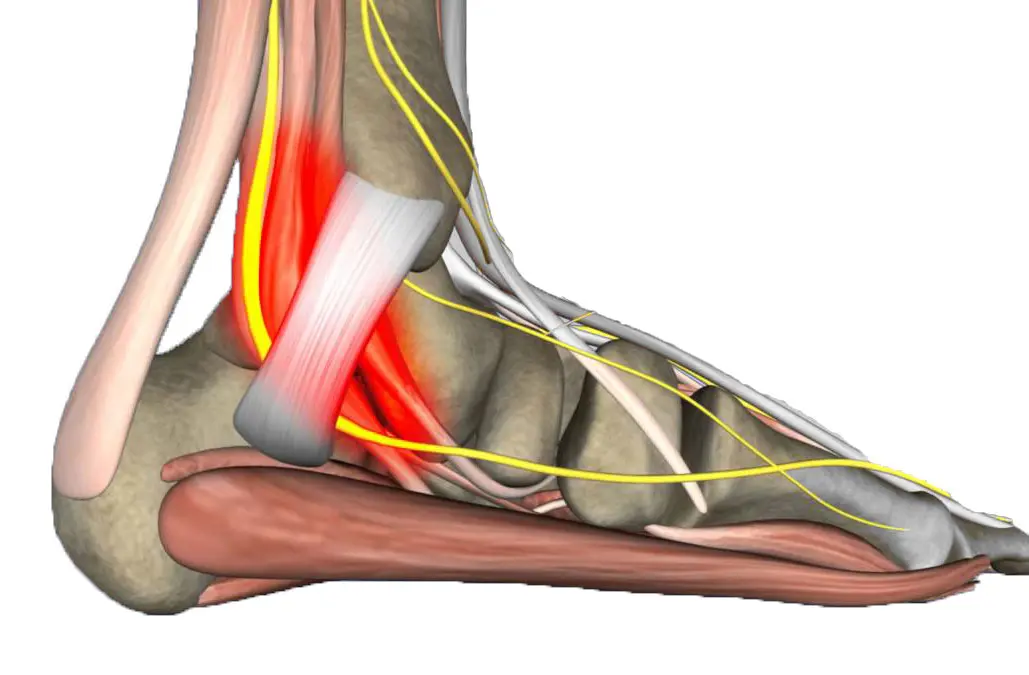

EXCELENTE A base de 255 reseñas Publicado en Lourdes Martinez AlbinTrustindex verifica que la fuente original de la reseña sea Google. Muy contenta con el trabajo y la simpatía de EneritzPublicado en Olga ArzaTrustindex verifica que la fuente original de la reseña sea Google. Son buenísimos profesionales y la,atención no puede se mejor. Les puntuó de 10Publicado en Bernardette BizkarguenagaTrustindex verifica que la fuente original de la reseña sea Google. He acudido a la clínica por una fascitis plantar, he estado muy cómoda y la atención ha sido magnífica. Y lo más importante el tratamiento me ha ido muy bien. Es muy recomendablePublicado en Azucena de Liras PalaciosTrustindex verifica que la fuente original de la reseña sea Google. Un trato fabuloso y muy buenas profesionalesPublicado en Ane UrrutiaTrustindex verifica que la fuente original de la reseña sea Google. No puedo estar más contenta. Tengo una malformación congénita en los pies que con el transcurso de los años está yendo a peor. Fui donde Gisela bastante desesperada y por fin hemos conseguido las plantillas que necesito. Hemos tenido que darle unas cuantas vueltas, pero por fin lo hemos conseguido para alegría de ella y por supuesto mía. Me ha animado en todo momento cuando me veía decaer y ha sido un gran apoyo. Si con mis pies lo ha conseguido, consigue lo que se proponga. Un saludo tmbn y una felicitación a sus compañeras, que siempre te reciben con una gran sonrisaPublicado en Javier 10Trustindex verifica que la fuente original de la reseña sea Google. Acudi al centro tras varios años dando vueltas en otros sitios por una fascitis plantar de dificil solución que me impedia realizar cualquier deporte de impacto y gracias a Gisela he podido retomar la actividad deportiva y dejar el problema que tenía con la fascitis olvidado

¿Sientes una molestia extraña entre los dedos del pie que no logras identificar? El dolor...